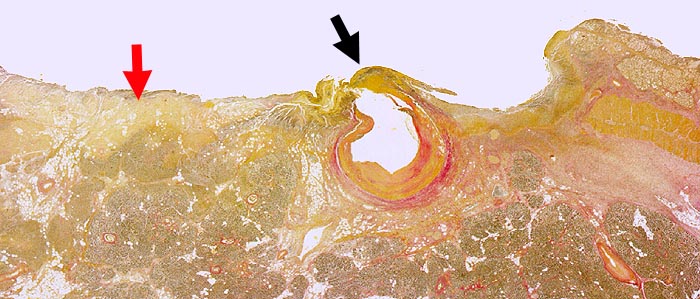

AP/ Chronisches Duodenalulkus

Chronisches Duodenalulkus

Entzündung / Reparatur

Darm, Anus

Duodenum